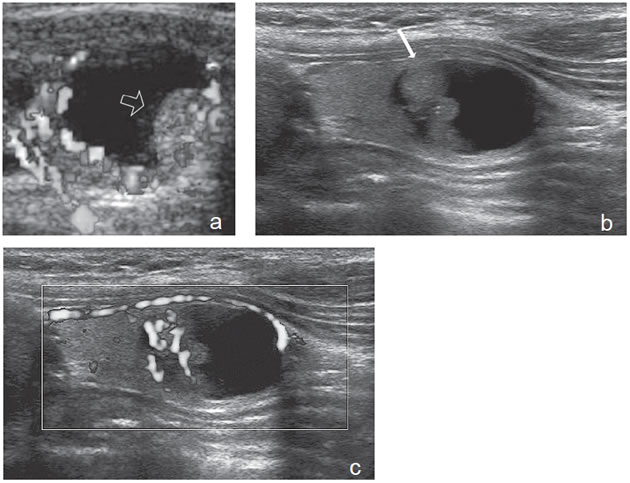

Un nódulo que tiene un componente quístico significativo, usualmente es un nódulo benigno hiperplástico, que ha acumulado abundante coloide (Figura 2a) o bien, un nódulo sólido que ha experimentado un proceso de degeneración colicuativa o hemorragia (Figura 2b). El coloide o el contenido líquido de un nódulo se ve anecogénico (negro en la imagen ecográfica) y las estructuras sólidas se ven ecogénicas (distintos tonos de grises), siendo la ecogenicidad similar al del parénquima tiroideo. En un nódulo sólido la ecoestructura y la ecogenicidad pueden ser variables. En general, la frecuencia de carcinoma es muy baja en nódulos quísticos13 y la mayoría de los carcinomas se presentan como nódulos sólidos (Figura 2c).

Figura 2. a) Quiste coloideo anecogénico y focos ecogénicos (flecha) con artefacto en cola de cometa; b) Nódulo mixto sólido-quístico (cabezas de flechas). Imagen vegetante (flecha) adherida a un tabique que se proyecta al lumen; c) Comparación entre el aspecto ecográfico de un cáncer papilar sólido (flecha abierta) y un quiste coloideo anecogénico.